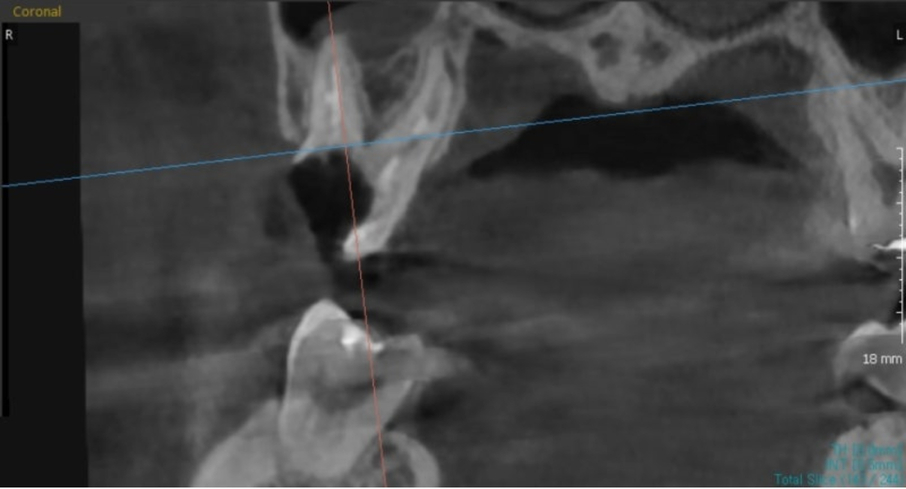

Tuy nhiên, trong trường hợp này

Vì tình trạng viêm nặng đến chân răng

▲ Viêm sâu nặng tận chân răng

Không thể phẫu thuật kéo chân răng ở trường hợp này

Điều trị cấy ghép Implant được thực hiện sau khi nhổ răng.

▲ Điều trị cấy ghép Implant sau khi nhổ răng bị sâu đến tận chân răng do mão răng cũ